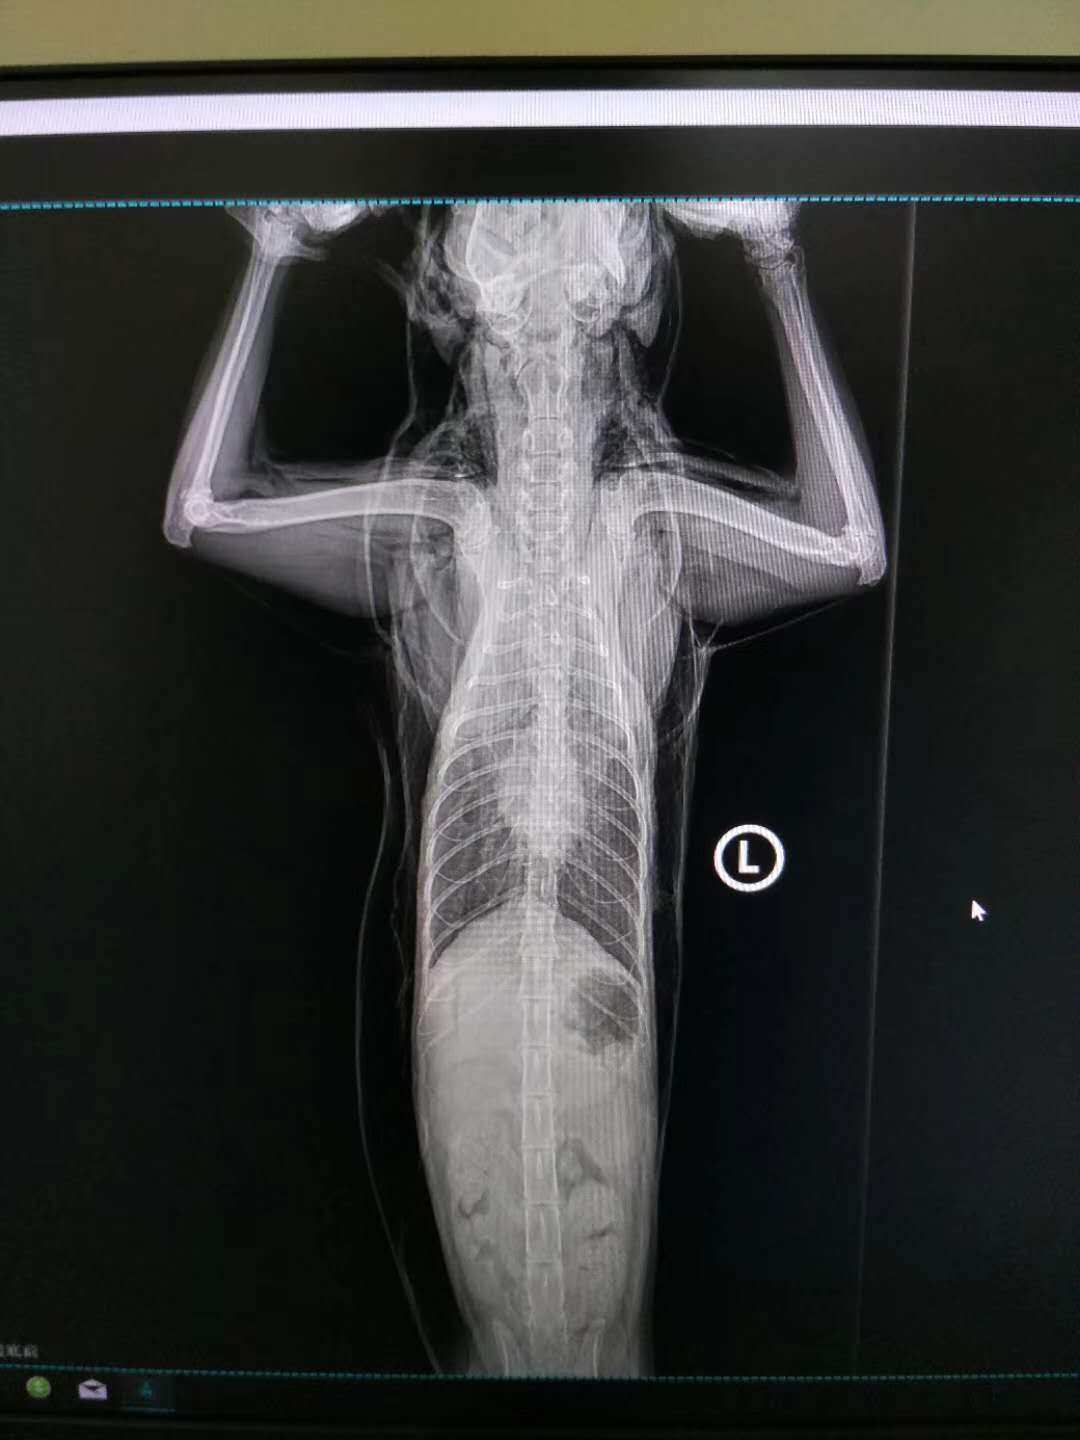

轉(zhuǎn)院全身氣腫病例治愈出院:暹羅貓,發(fā)財(cái),近期在其他醫(yī)院做的絕育手術(shù),術(shù)后出現(xiàn)全身氣腫(第2,第3張照片為原醫(yī)院拍攝),轉(zhuǎn)賬至我院,經(jīng)我院檢查發(fā)現(xiàn),在貓咪氣管入胸段,約有5.6mm大小孔洞,氣體延此孔泄露,并移行到頸部背測,接入皮下疏松結(jié)締組織,進(jìn)一步擴(kuò)散至全身。推測可能與絕育手術(shù)呼吸麻醉時(shí)氣管插管不當(dāng)有關(guān)。我院采取壓迫保守療法,住院10天,痊愈出院。PS:寵物主人選擇醫(yī)院時(shí),一定要慎重,就診時(shí)關(guān)鍵是大夫水平,其他是次要因素。